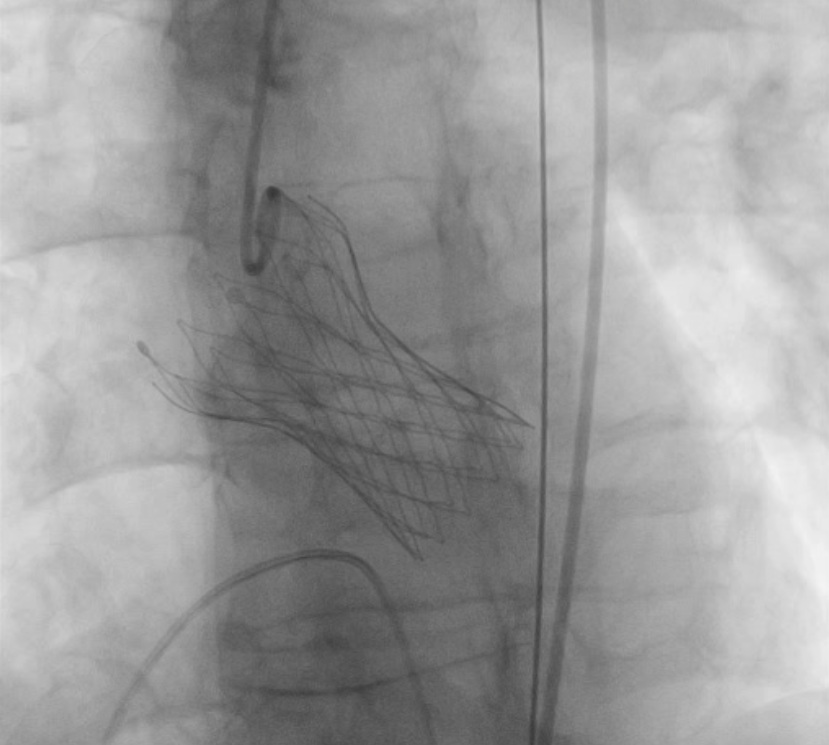

6月21日下午,楚天舒主任团队成功为患者进行了TAVR换瓣治疗。手术中,通过主动脉根部造影,可见患者的主动脉瓣活动僵硬,已不能很好开阖。通过导管测量得到植入前心室主动脉压力差接近100mmHg,提示主动脉瓣狭窄已严重阻碍心脏正常泵血工作。人工瓣膜成功植入后,可见人工瓣膜瓣叶开阖自如,心脏对外泵血压力明显减轻,导管测得压力阶差降至8mmHg。这提示着患者的主动脉瓣狭窄情况,已较前大为缓解,手术圆满成功。术后患者生命体征平稳,带气管插管安全返回ICU特护。一天后,患者转回心血管内科二病区继续治疗。目前,已顺利出院。

TAVI的操作方法有点类似于在动脉内放置支架,通过导管将一个完全可折叠的人工瓣膜送到主动脉瓣部位。一旦此人工瓣膜释放,扩张,就会把原有的病变的瓣膜瓣叶推开,新的瓣膜中的瓣叶等结构,就会替代原有瓣膜的功能,接管主动脉瓣原有的调节血液流动的工作。